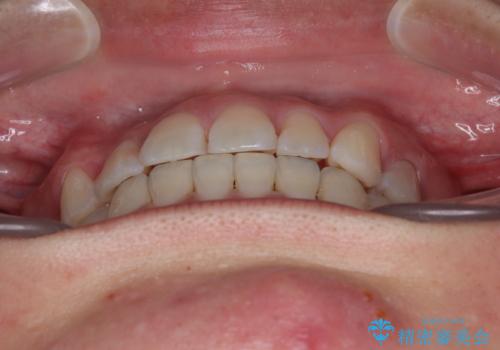

上下前歯のデコボコを気にして来院された患者様です。

ワイヤー矯正でもマウスピース矯正でも可能でしたが、短期間で、自身の手を煩わせることなく治療を行いたいとのことで、ワイヤー装置にて矯正治療を行うこととしました。

舌の突出癖により、治療過程でスペースが多くできましたが、舌のトレーニングを頑張っていただき、1年強で終えることができました。